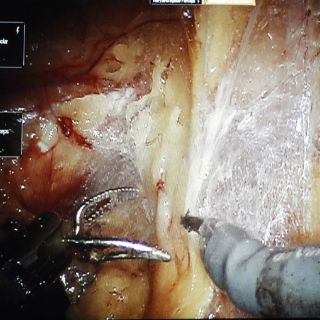

Pero en pruebas pequeñas con cerdos, el brazo robótico realizó sutura de tejido intestinal tan bien, y en algunos casos incluso un poco mejor, que algunos cirujanos que compitieron con el dispositivo, reportaron investigadores en la revista Science Translational Medicine.